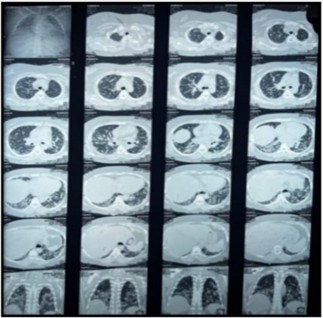

Bilateral coarse crackles were noted upon chest auscultation, suggesting possible interstitial lung involvement. A comprehensive set of laboratory tests was performed. The results indicated significantly elevated CPK levels at 1250 U/L (normal range: 20-75 U/L), and a serum aldolase level of 10 U/L (normal: <7.60 U/L). The ENA profile was particularly noteworthy for positive Anti-Jo-1 antibodies (96 U/L, normal: 6-12 U/L) and Anti-SSA/Ro 52 antibodies (67 U/L, normal: 6-12 U/L), while the remainder of the ENA profile, including rheumatoid factor (10 U/L), ANA, and anti-CCP, returned negative results. HRCT chest showed features of interstitial lung disease consistent with a NSIP pattern, including bilateral ground-glass opacities more pronounced in the lower lobes, interstitial septal thickening, and increased attenuation in a reticular pattern, with preserved lung volumes and no honeycombing (Figure 03). ACE levels were within normal limits at 32.4 U/L (normal: 8-65 U/L). Bronchial biopsy indicated benign respiratory mucosa with no malignancy, and echocardiography demonstrated normal biventricular systolic function with an ejection fraction of 62%.

Figure 3: HRCT Chest: NSIP pattern with bilateral ground-glass opacities, interstitial septal thickening, and reticular attenuation